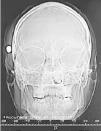

Fig. 1. Fig. 2.

Varón de 34 años que, tras una reyerta callejera, sufre herida por arma de fuego en zona craneofacial sin pérdida de conciencia. Al ingreso en la unidad de cuidados intensivos el paciente se encuentra somnoliento con apertura ocular a la llamada, lenguaje y movilidad normales. Presenta epistaxis bilateral, hematoma en anteojos y herida en ala nasal izquierda de unos 8 mm de diámetro, palpándose cuerpo extraño subcutáneo en zona retroauricular derecha. La radiografía simple de cráneo (fig. 1) demuestra la existencia de un proyectil en región temporal derecha. En la tomografía axial computarizada craneal (fig. 2) se identifica un trayecto intraparenquimatoso con sangre y aire en lóbulo temporal derecho orientado hacia una fractura de la calota craneal, quedando el proyectil alojado en los tejidos blandos inmediatos a la fractura. El hemisferio cerebral derecho muestra discreta expansividad. A pesar de la gravedad de las lesiones el paciente fue dado de alta 3 semanas después (escala de coma de Glasgow de 15), sin presentar ninguna complicación posterior.